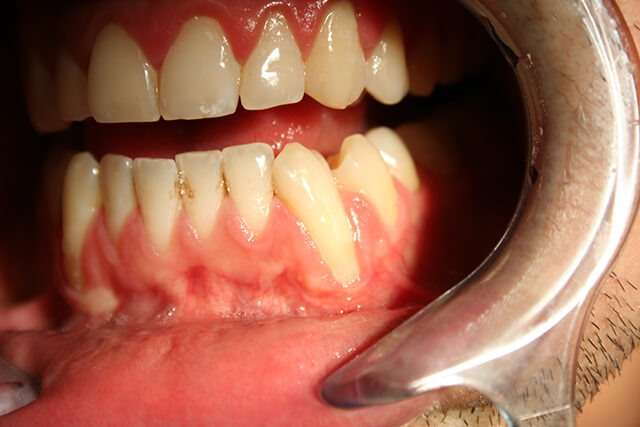

歯と歯ぐきのキワが下がってきた

歯のWSD(楔状欠損)や咬耗、歯周病、歯茎の下がりが見当たらない人で、知覚過敏の人や、顎関節症の人はこれにあてハマるんだよ。こういう人は、夜間マウスピースしたって良くならないから厄介だね。

根面、象牙質露出ないのに症状ある人は